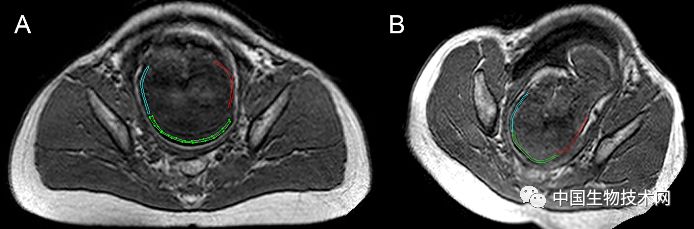

胎头成型和第二产程期间的头部形状变化 图片来源:《PLOS ONE》

在这项新研究中,为了证明和描述胎头成型和分娩过程中大脑形状的变化,Olivier Ami博士领导的研究团队使用三维MRI捕捉了7名胎儿在分娩前和第二产程中头骨和大脑的详细图像。该分析揭示了所有7名胎儿在第二产程都有胎头成型,其中颅骨的不同部位存在不同程度地重叠。其中5名新生儿的头骨和大脑形状恢复到出生前的状态,但另外2名新生儿的头骨和大脑形状仍在变化。胎头成型程度最高的三名新生儿中有两名是通过紧急剖腹产手术分娩的,另一个是通过阴道分娩的。

图片来源:《PLOS ONE》